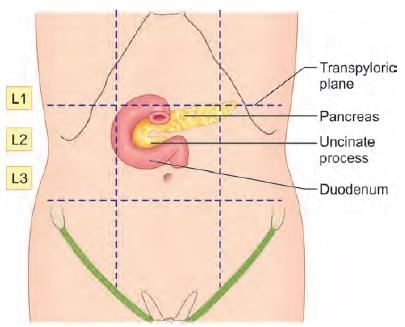

Anterior relations of third part of duodenum are all, except: (INI-CET May 2023)